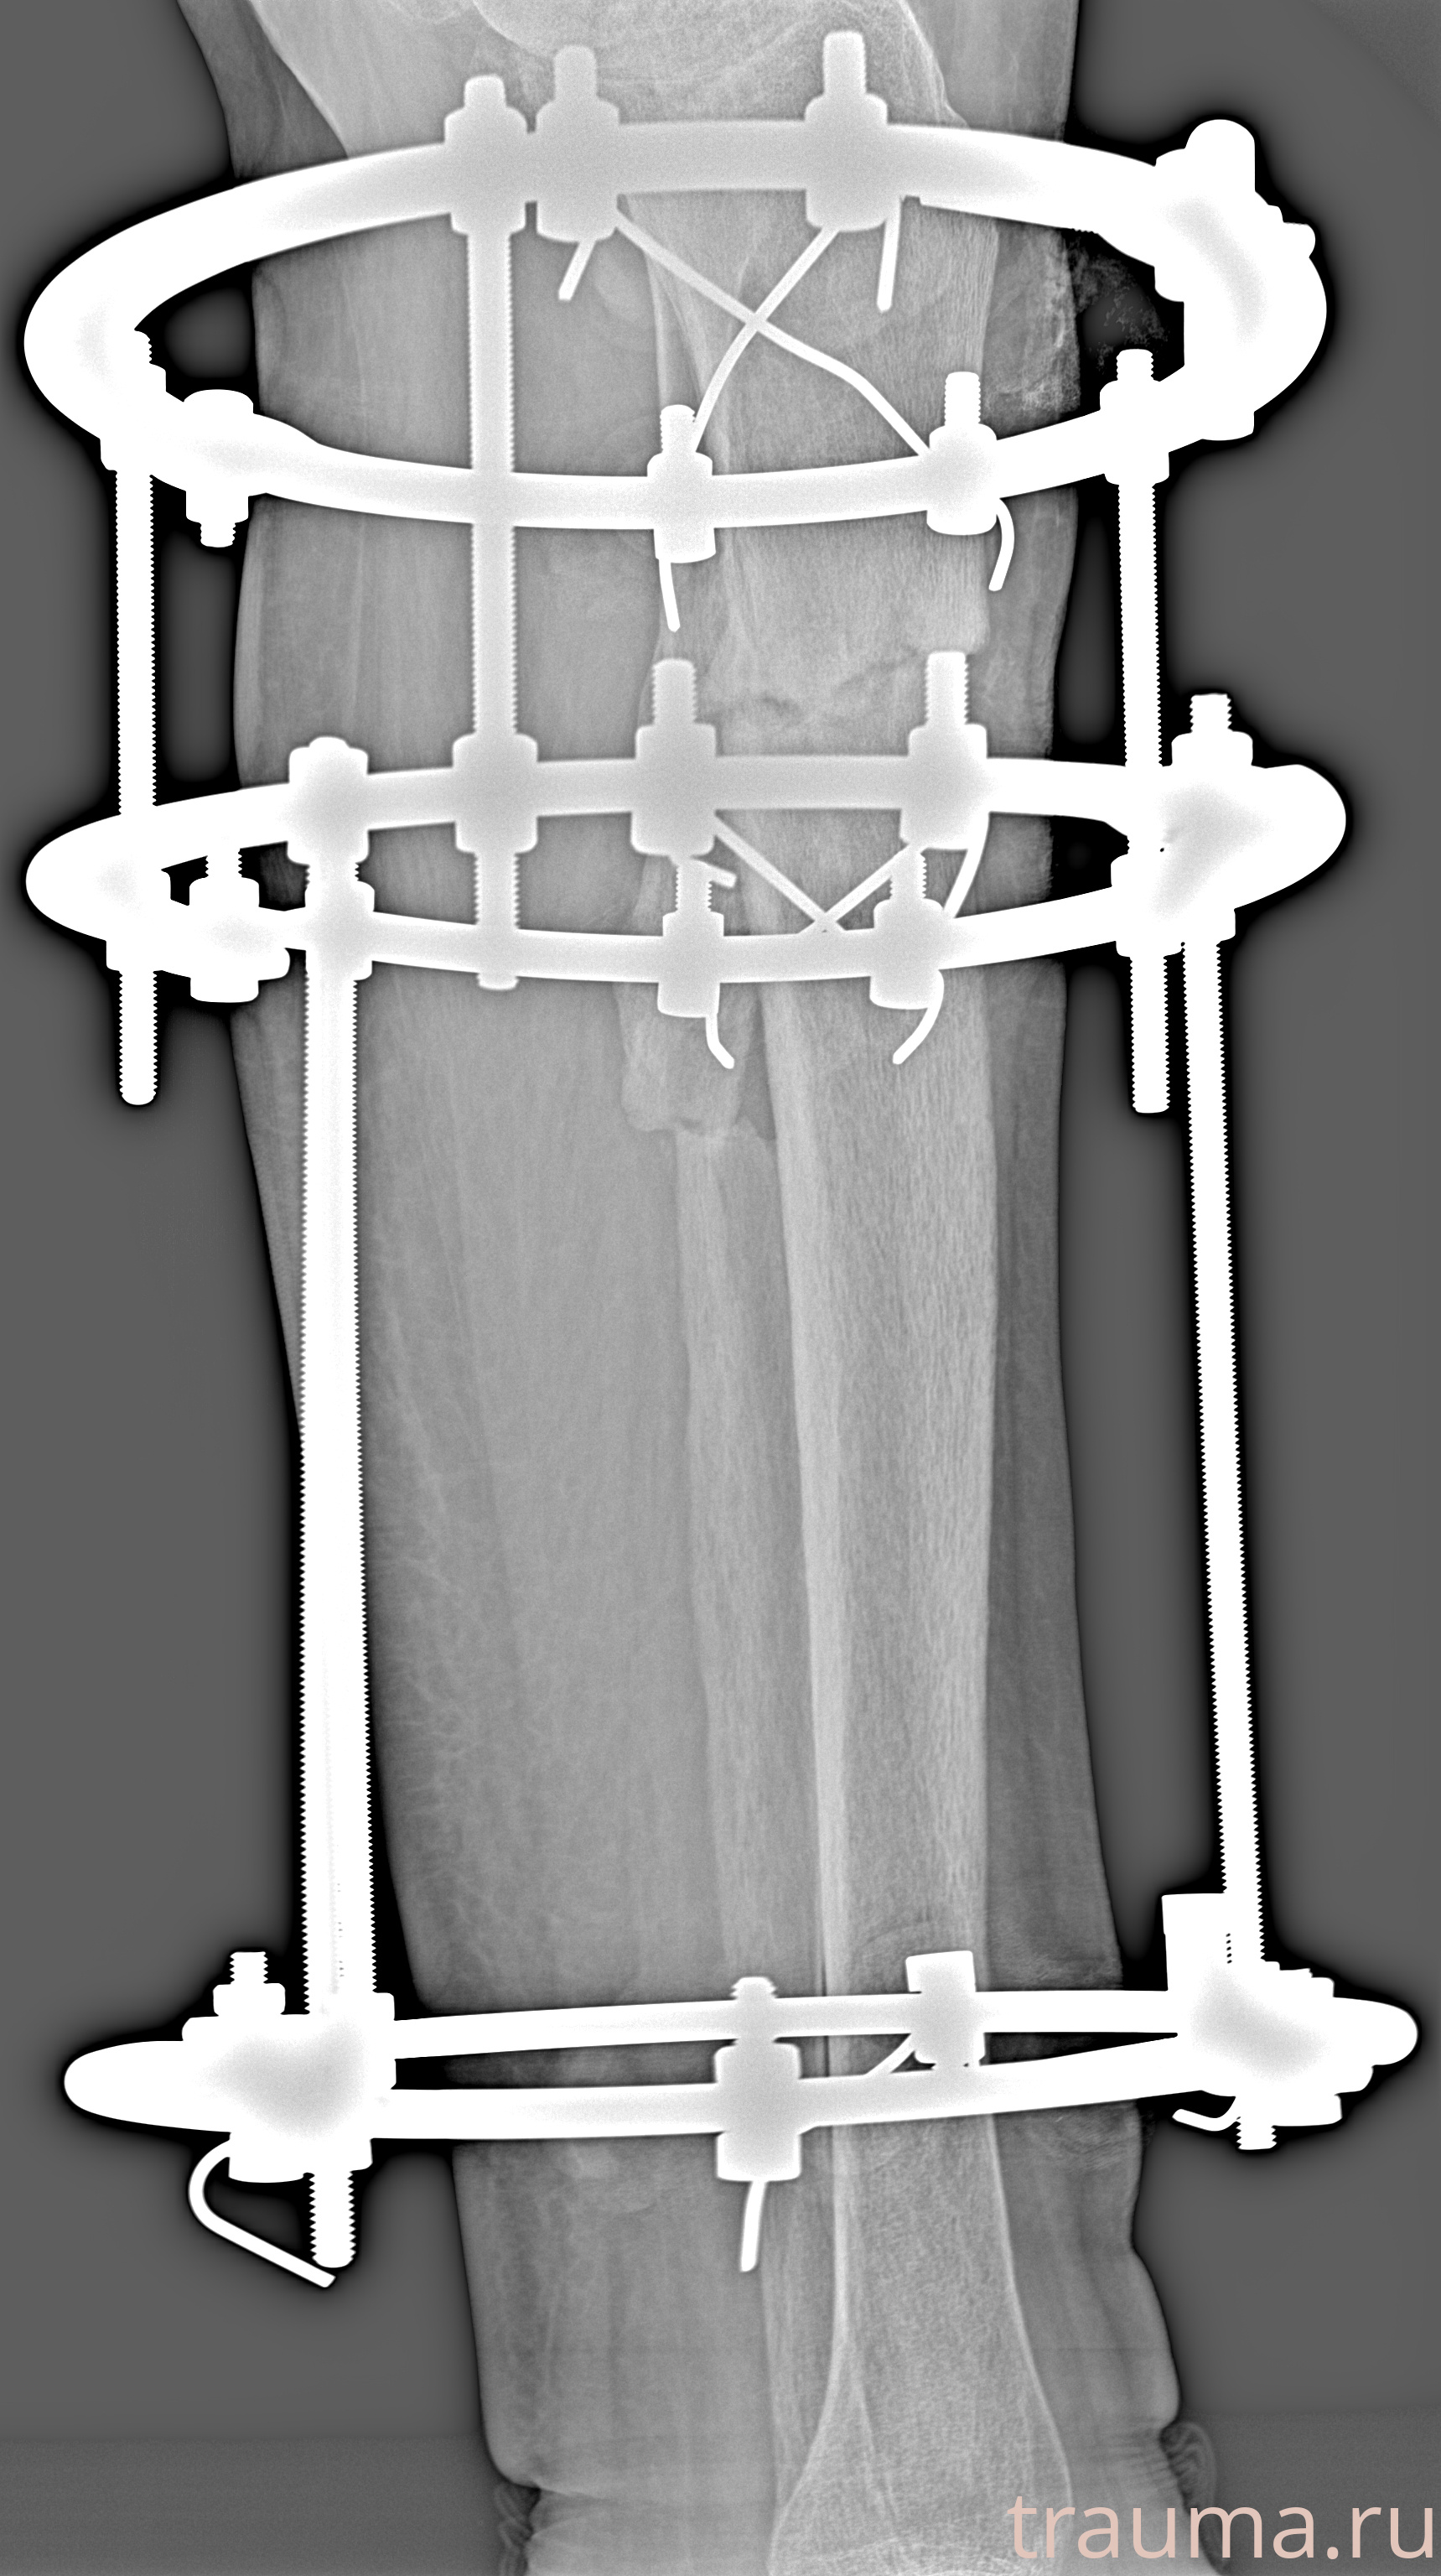

Рентгенограммы

Рентген на дому: по вашему адресу приезжает врач-рентгенолог, травматолог-ортопед с мобильным рентгеновским аппаратом, проводит диагностику травмы или заболевания, делает необходимые рентгенограммы, дает рекомендации по дальнейшему лечению. Получить качественные снимки в домашних условиях возможно благодаря уникальной методике, разработанной МосРентген Центром для института  Склифосовского